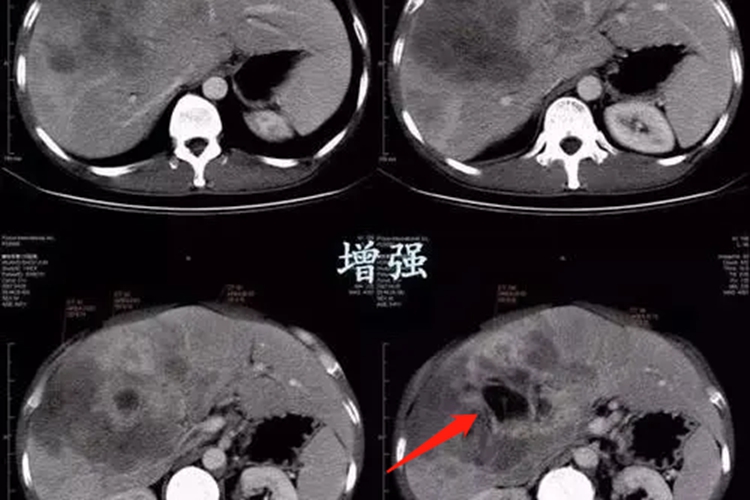

黑色素瘤晚期表现为瘤体溃疡、结痂、出血或变硬,迁延不愈,周围出现卫星灶,并通过淋巴转移引起腹股沟等部位的淋巴结肿大,还可通过血流转移至其他器官,如转移至肝,引起阵发性上腹部疼痛,CT检查可见肝内单发或多发稍高密度结节,伴钙化。